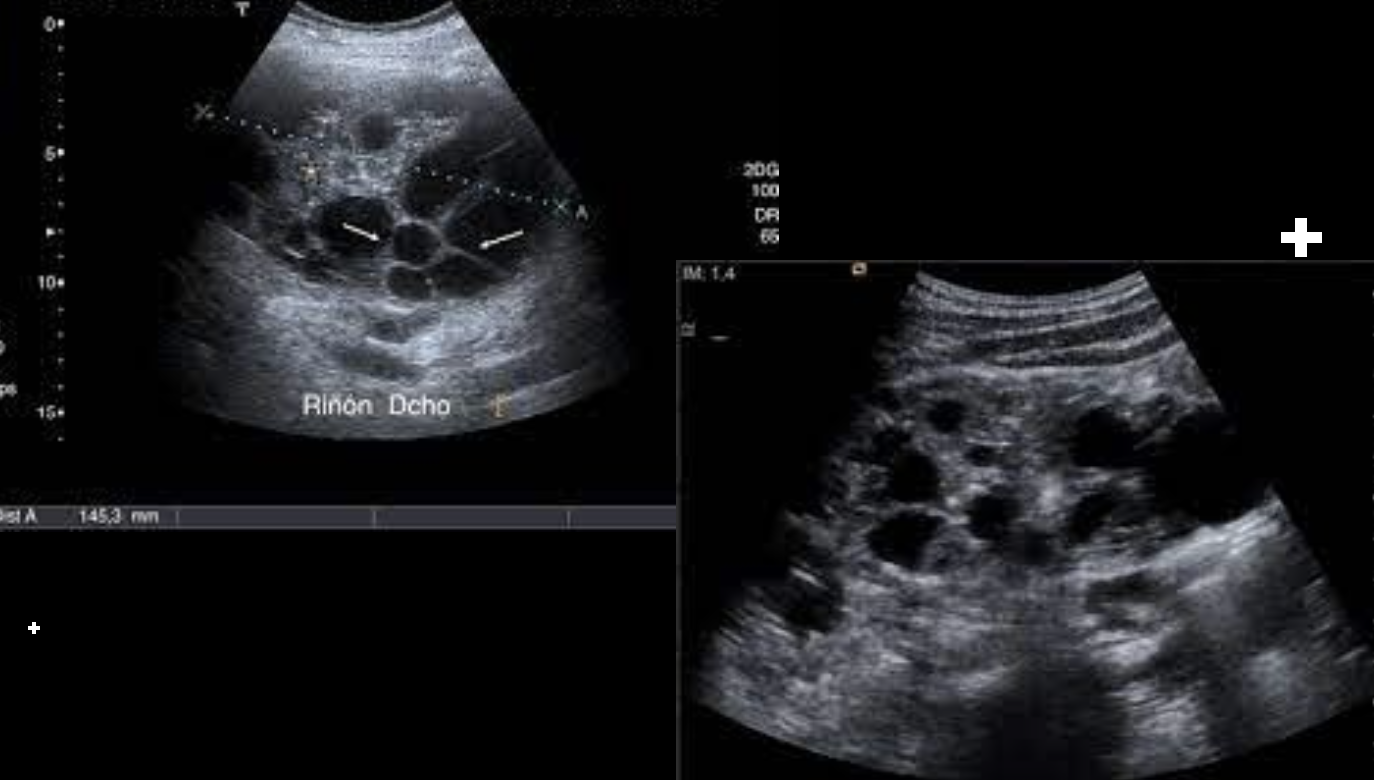

US

Hidronefrosis

Quistes renales